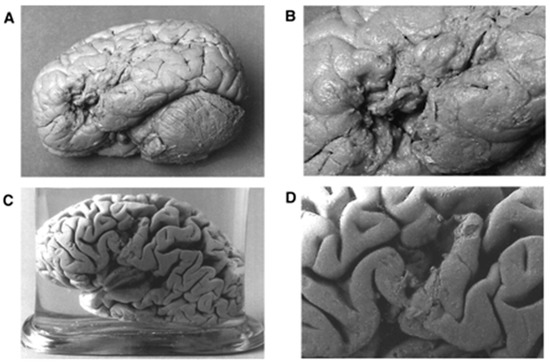

- Lorch, M. Re-Examining Paul Broca’s Initial Presentation of M. Leborgne: Understanding the Impetus for Brain and Language Research. Cortex 2011, 47, 1228–1235. [Google Scholar] [CrossRef]

- Rorden, C.; Karnath, H.O. Using Human Brain Lesions to Infer Function: A Relic from a Past Era in the FMRI Age? Nat. Rev. Neurosci. 2004, 5, 812–819. [Google Scholar] [CrossRef]

- Zihl, J.; von Cramon, D.; Mai, N. Selective Disturbance of Movement Vision after Bilateral Brain Damage. Brain 1983, 106, 313–340. [Google Scholar] [CrossRef]